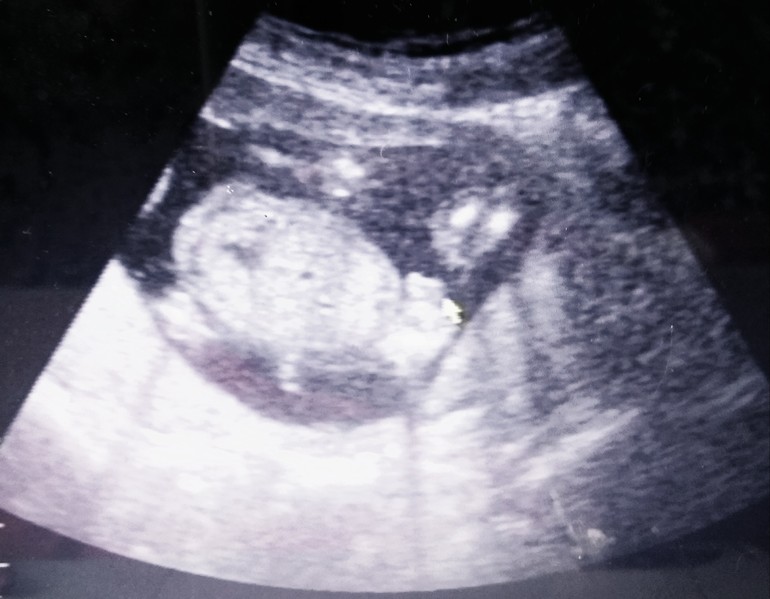

12.02.18 - перед первым скринингом решила сходить на УЗИ. Пошла в 11недель и 3 дня, по УЗИ мы опять опережаем, 12 и 2)) итак: КТР 52мм, твп1,4мм, носовая кость 2мм, чсс176 . Сказали хороший здоровый малыш))) пол пока не известен. Официальный скрининг 16.02 ровно в 12 недель. Интересно расскажут что то или нет?